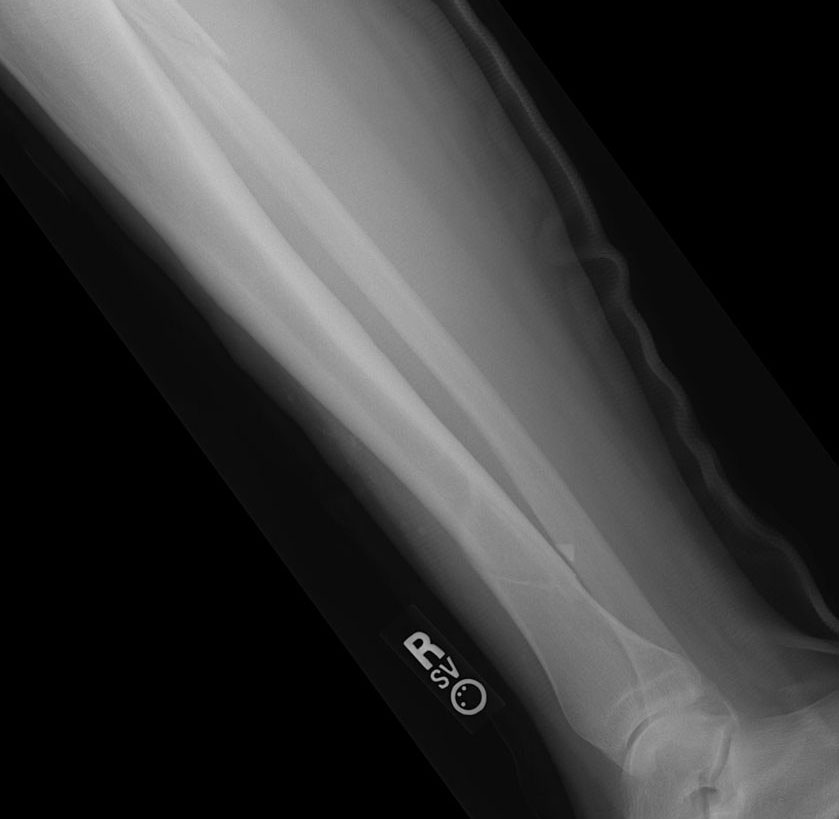

• Stress fracture of the tibia: small cracks in the bone on the inside of the lower part of the leg, usually a progression from shin splints

• Fibula fracture: a break or crack in the bone on the outside of the leg due to trauma